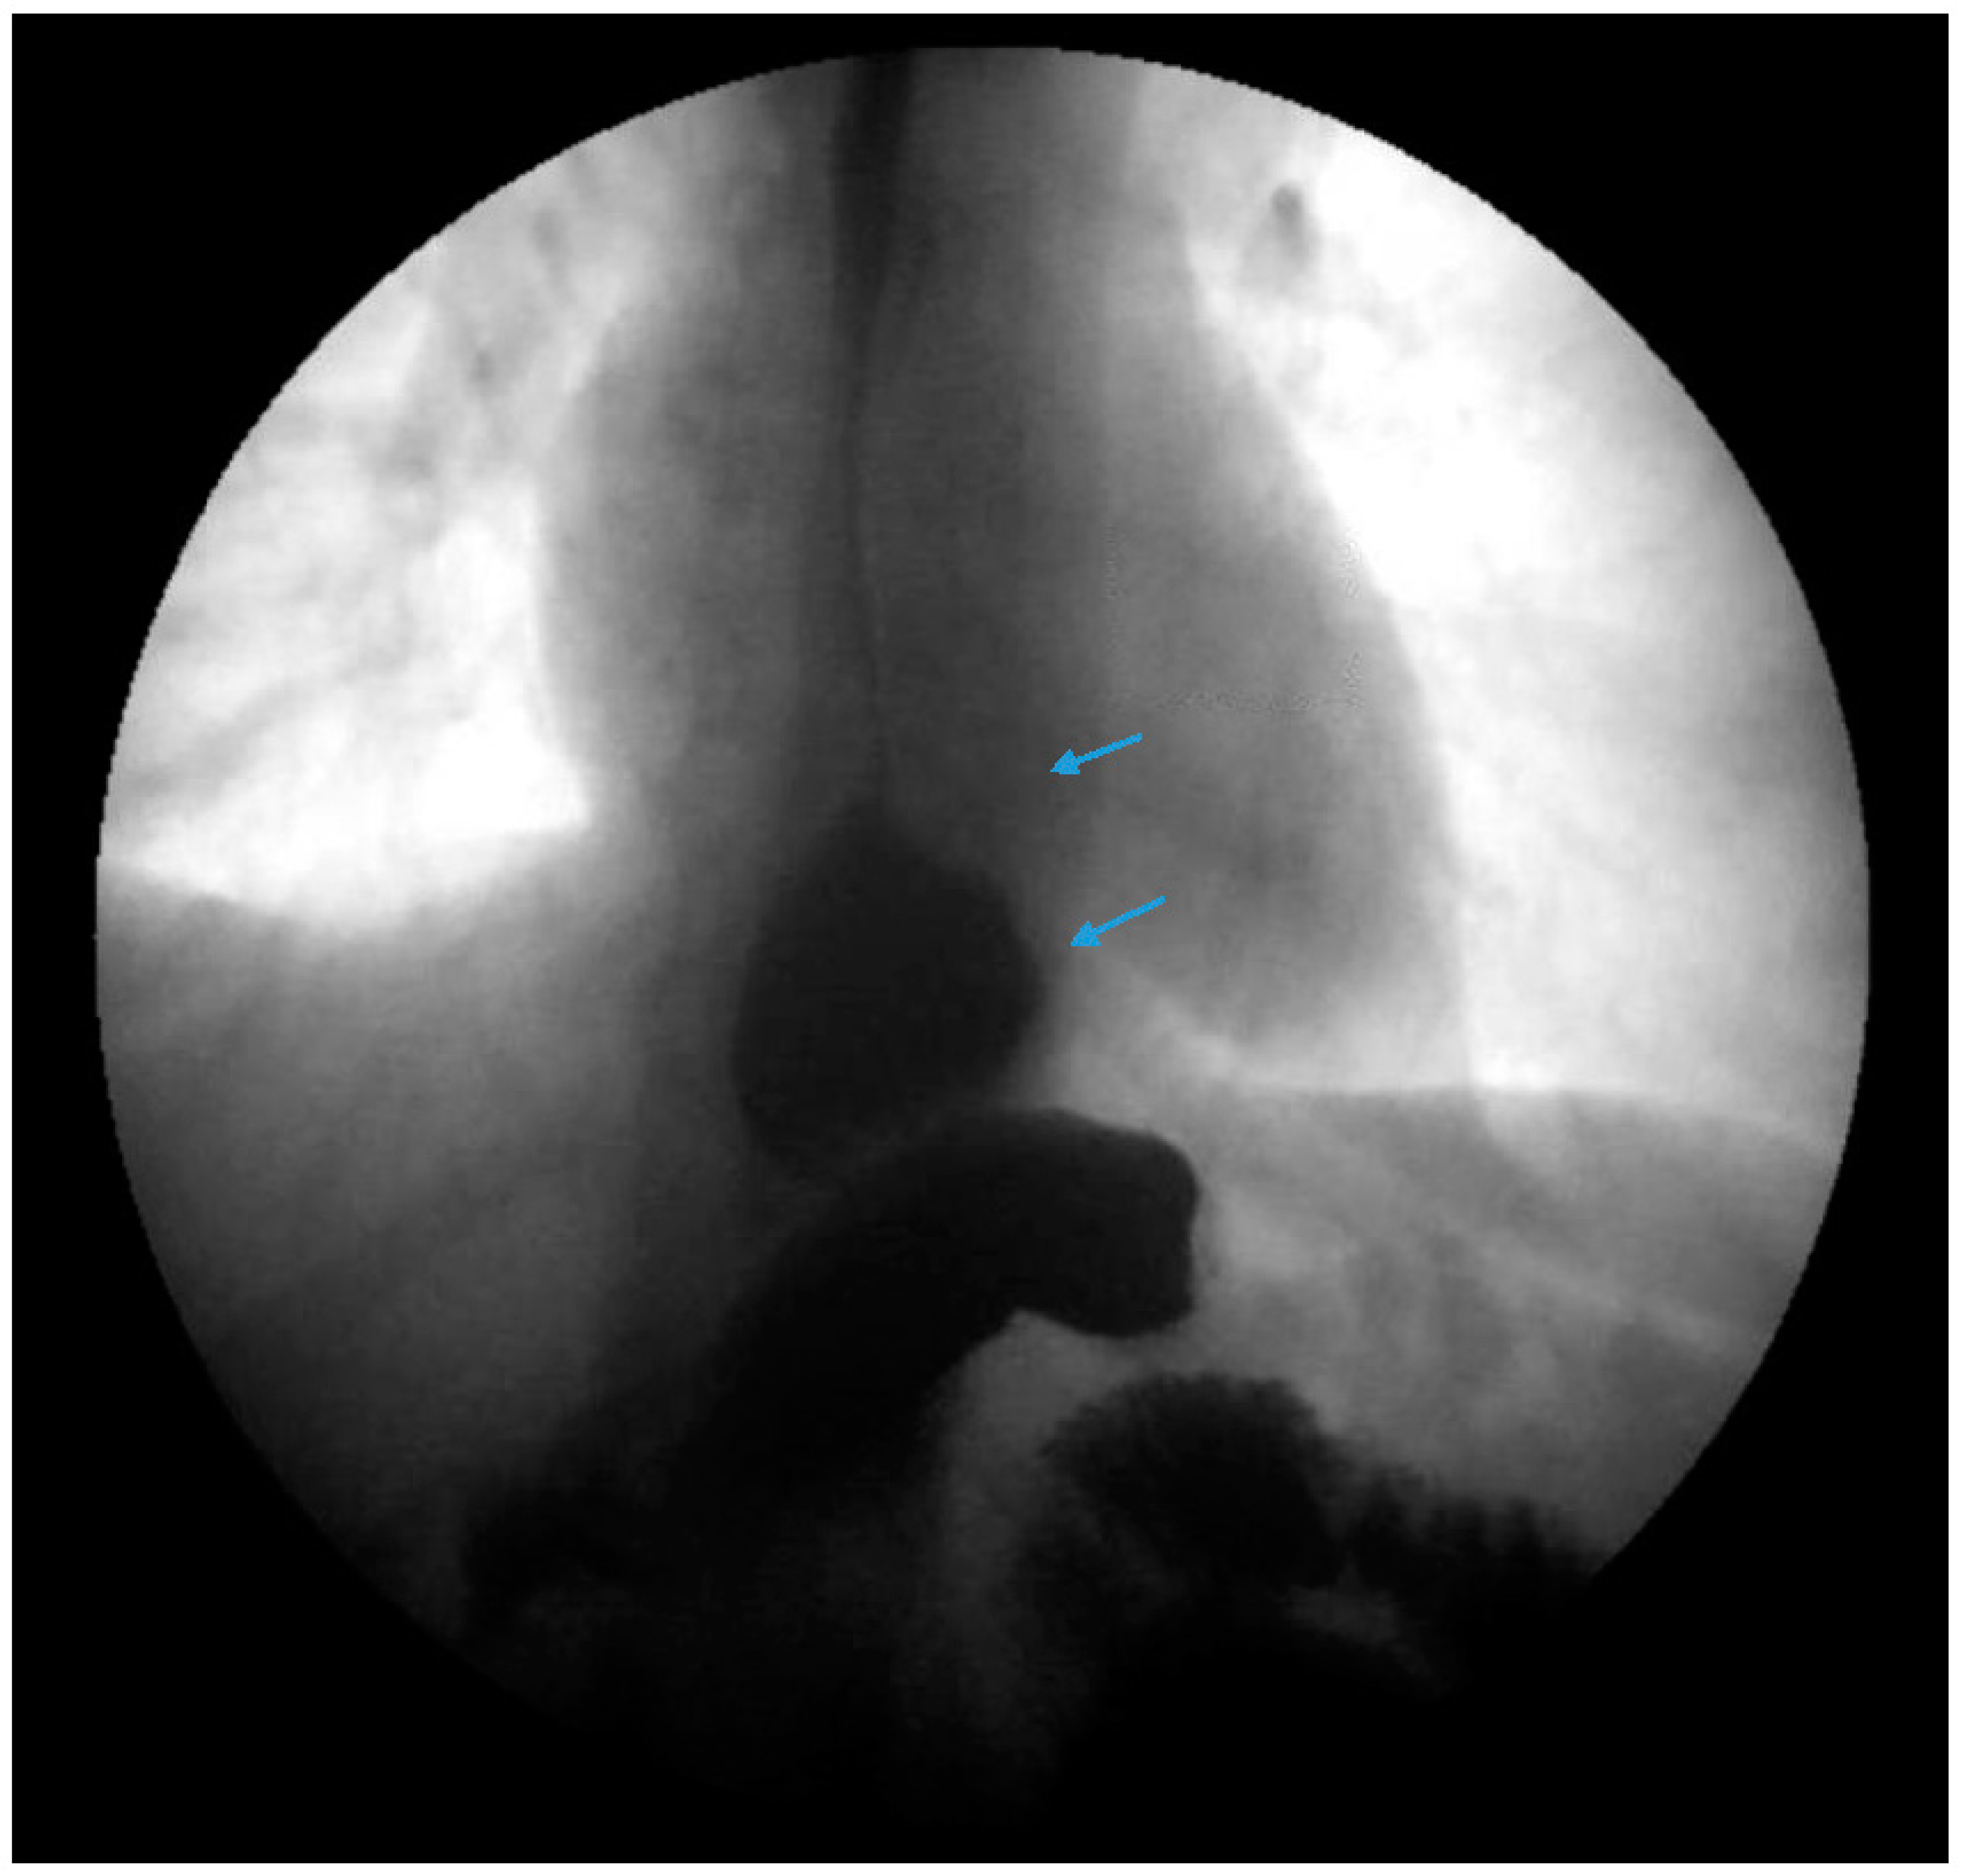

Figure 1. Upper gastrointestinal series in a patient post-sleeve gastrectomy with early satiety and reflux reveals the following: a small, hiatal hernia and gastroesophageal reflux (blue arrow, left) in addition to abnormal angulation (blue arrow, right) and dilation of the gastric sleeve (green arrow, right). The patient underwent conversion to Roux-en-Y gastric bypass with marked clinical improvement.